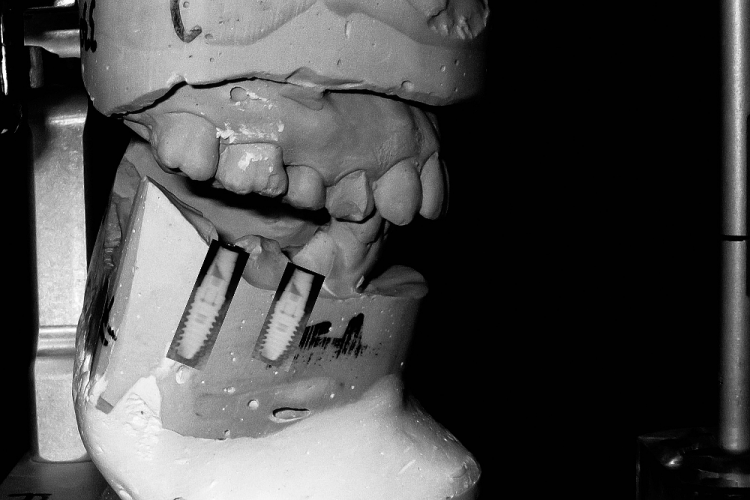

To assist the process, the mounting of a patient’s diagnostic casts remains an important step, as it allows the assessment of critical factors such as occlusion, implant position and forces direction.[2] It also allows exploration into prosthetic options,[2] such as angled abutments (Fig. 1).

Fig. 1: Implant treatment planning

Laboratory

If the clinician has delegated mounting to the laboratory, then the records phase has been completed. The following applies to those who mount their own casts. Position the tablet in the stand 6 to 12 inches from the cast and launch the VF app. Place the maxillary cast on the articulator mount (Fig. 9). The patient image will appear.

Adjust orientation of cast (tilt) to confirm alignment with the patient markers. Verify orientation of midline, incisal edges, occlusal plane and facial references (Fig. 10).

When the cast is correctly positioned, simply take a photo. Resize and reposition the image if required and save the image. Orientation can be confirmed by altering the transparency of either the face or cast image. Mount the maxillary cast to the upper articulator. The record of occlusal contacts (Fig. 8) will then be displayed. Position the mandibular cast to the maxillary cast, confirming contacts,and mount the mandibular cast.

The VF will then generate a composite of the skull, face and cast. The operator has the ability to alter the transparency of any image to reconfirm the position of the skull to the patient’s face and, ultimately, to the cast (Fig. 11). The laboratory component has been completed (Fig. 12).